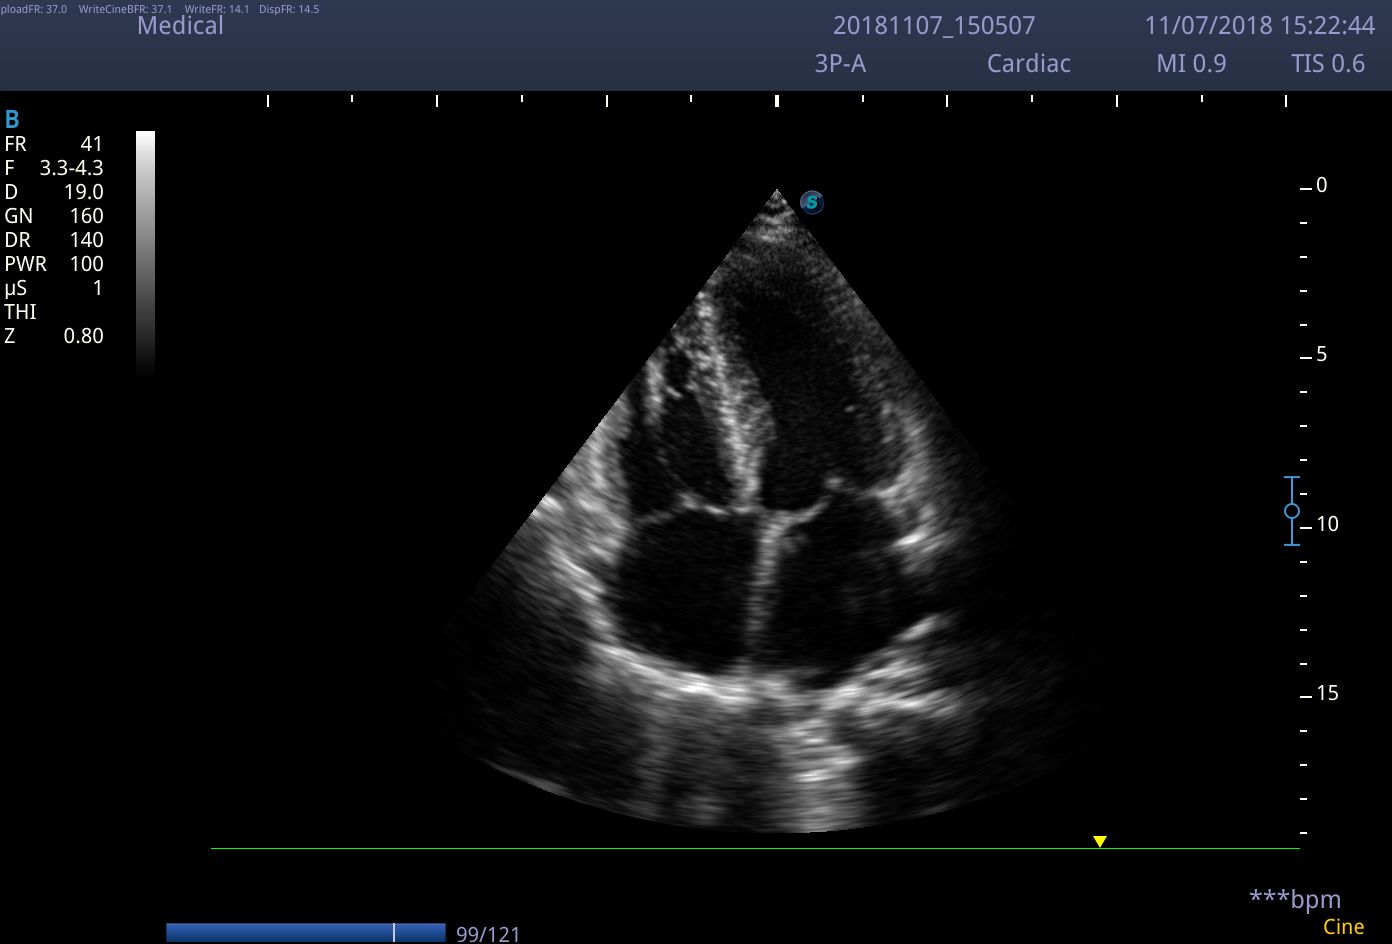

Chuyên biệt cho chẩn đoán tim mạch

- M-mode và Anatomical M-mode: đánh giá cấu trúc tim theo thời gian thực.

Máy siêu âm SonoScape P9 là thiết bị hiện đại ứng dụng rộng rãi trong lĩnh vực y tế, đặc biệt nổi bật trong chẩn đoán tim mạch. Với công nghệ quét 2D tiên tiến, máy cung cấp hình ảnh sắc nét, giúp bác sĩ quan sát chi tiết cấu trúc tim như van tim, cơ tim và nhĩ tim. Ngoài ra, máy còn tích hợp các chế độ Doppler màu, Doppler mạch máu, hình ảnh thời gian thực và tính năng giảm nhiễu, hỗ trợ phát hiện bệnh lý tim mạch một cách nhanh chóng và chính xác.

✔ Chẩn đoán bệnh lý tim mạch: Siêu âm tim qua thành ngực, đánh giá hẹp động mạch, hở van tim, đo vận tốc dòng máu.

Chất lượng hình ảnh 2D trên máy siêu âm chuyên tim SonoScape P9: